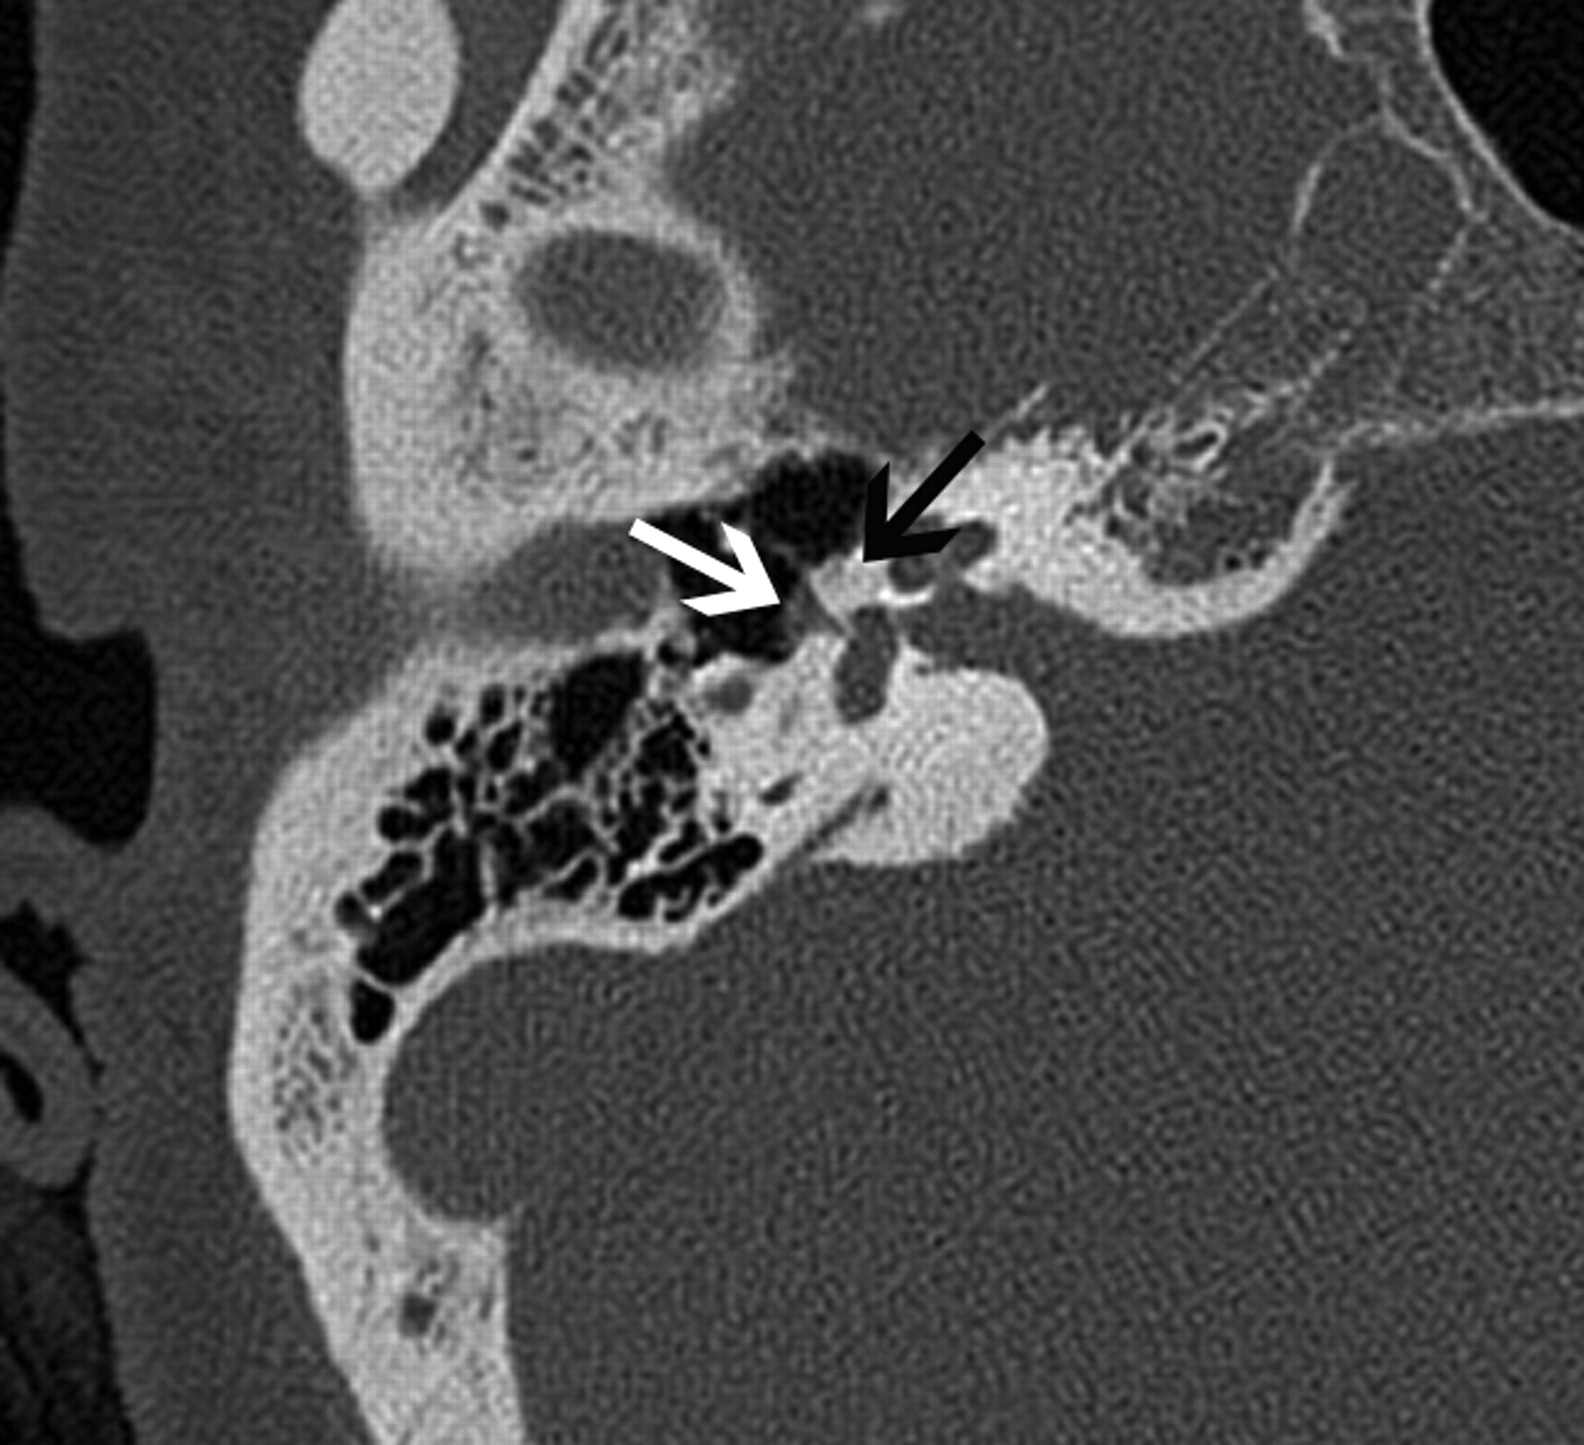

Glomus tumors are vascular paragangliomas located in close proximity to cranial nerves. Glomus tympanicum, the most common tumor of the middle ear cavity, usually arises along the course of the tympanic nerve (Jacobson nerve). Glomus tumors are most frequently located on the cochlear promontory (Fig 1) but can arise almost anywhere in the medial mesotympanum.18 The typical appearance of a glomus tumor on temporal bone CT is a round mass based on the cochlear promontory. On MR imaging, these tumors show intense enhancement. Glomus tympanicum usually does not cause erosion of the underlying bone; if the floor of the middle ear cavity is eroded, a glomus jugulotympanicum should be considered (described in the section on jugular foramen masses). Unlike paragangliomas elsewhere in the body, glomus tumors are usually solitary, and the detection of such a lesion does not indicate a need for further imaging to search for additional tumors.

Glomus tympanicum (arrow) in a 30-year-old woman with right-sided pulsatile tinnitus. Axial CT image demonstrates lobulated soft-tissue attenuation in the middle ear overlying the cochlear promontory.